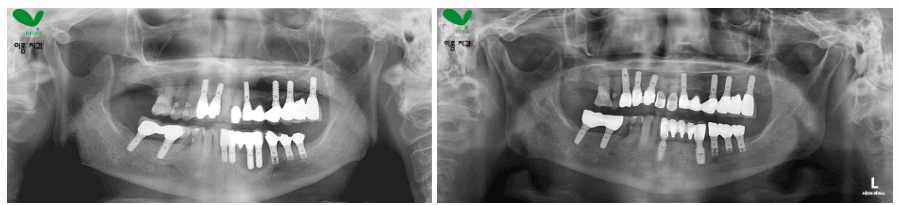

실제 사례로 보는 ‘뼈이식과 재식립’ 과정

한 환자분은 “기존 임플란트가 흔들린다”며 내원하셨습니다.

CT 촬영 결과, 발치 후 오랜 기간 방치하면서

상악 어금니의 뼈가 거의 흡수된 상태였죠.

게다가 상악동이 넓게 자리해 일반 식립이 불가능했습니다.

이에 **상악동 거상술(Sinus Lift)**을 병행하여

부족한 뼈 높이를 확보한 뒤 새로 임플란트를 식립했습니다.

수개월의 치유 기간을 거쳐 골유착이 안정적으로 확인되었고,

환자분은 다시 편안하게 어금니로 음식을 씹을 수 있게 되었습니다.

이처럼 ‘뼈이식 임플란트’는 단순한 보강이 아니라,

장기적인 성공을 결정짓는 핵심 단계입니다.